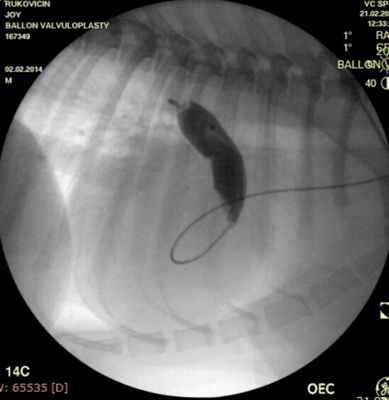

Проведено: баллонная вальвулопластика клапана легочной артерии (Тип А). Баллон Cordis maxi 40х20 мм. Инфляция до 5 атм. 10 попыток.

Показанием к оперативному лечению служит градиент систоличесокого давления на клапане легочной артерии свыше 50 мм рт.ст. При наличии дисплазии створок клапана — показана хирургическая коррекция порока, в остальных случаях возможно эндоваскулярное лечение. Операция выполняется в большинстве случаев под в/в анестезией, за исключением новорожденных, находящихся в критическом состоянии, у которых операция выполняется пол общим обезболиванием. Суть операции заключается в том, что после пункции бедренной вены в полость правого желудочка проводится и устанавливается катетер, далее проводник через клапан легочной артерии проводится в дистальные отделы легочной артерии. По проводнику в последующем проводится баллонный катетер и выполняется вальвулопластика. В настоящее время операция не сопровождается развитием летальных исходов и осложнений. Госпитальный период ограничен 3 днями.